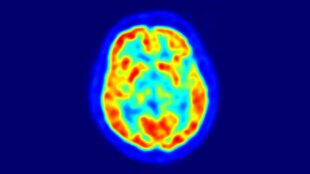

Nytt sätt att avbilda Alzheimers sjukdom – öppnar för utveckling av läkemedel

Tau-PET är en ny och lovande avbildningsmetod vid Alzheimers sjukdom. En fallstudie från Lunds universitet bekräftar nu också att tau-PET-bilderna stämmer väl överens med de verkliga förändringarna i hjärnan. Enligt forskarna bakom studien ökar därmed möjligheterna att utveckla...

Antikropp som PET-spårämne ger exaktare Alzheimers-diagnos

Forskare har för första gången lyckats få en antikropp att passera blodhjärnbarriären och fungera som spårämne vid PET-avbildning av hjärnan. Resultatet blev mer exakt information än med vanliga radioaktiva spårämnen. Studien ger hopp om effektivare diagnostik vid tidig Alzheimers...

Nu ökar möjligheterna att upptäcka alzheimers i tidig fas

En i Sverige nyligen godkänd metod för att leta efter tidiga tecken på Alzheimers sjukdom med så kallad amyloid PET-kamera fungerar lika bra som det ryggvätskeprov som används sedan tidigare. Det visar en studie från Lunds universitet. Forskningsresultaten ger hopp om tidig behandling för...